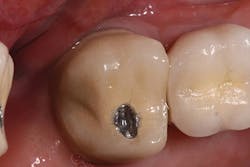

My first step in treatment was to create an access hole in the central fissure, where I then inserted a 2 mm reduction bur (Kometas, www.occlusalbur.com). In my opinion, this is the only way to guarantee adequate reduction to a tooth during preparation (Fig. 3). As you can see in Fig. 4, there does appear to be adequate clearance from a side view. However - and I cannot emphasize this enough - there is a significant difference between occlusal clearance and occlusal reduction. Fig. 5 clearly shows the preparation mark remaining following penetration with the 2 mm reduction bur mentioned previously. Following final preparation, another photo was taken from the side showing the preparation following adequate reduction (Fig. 6).

FIG. 3